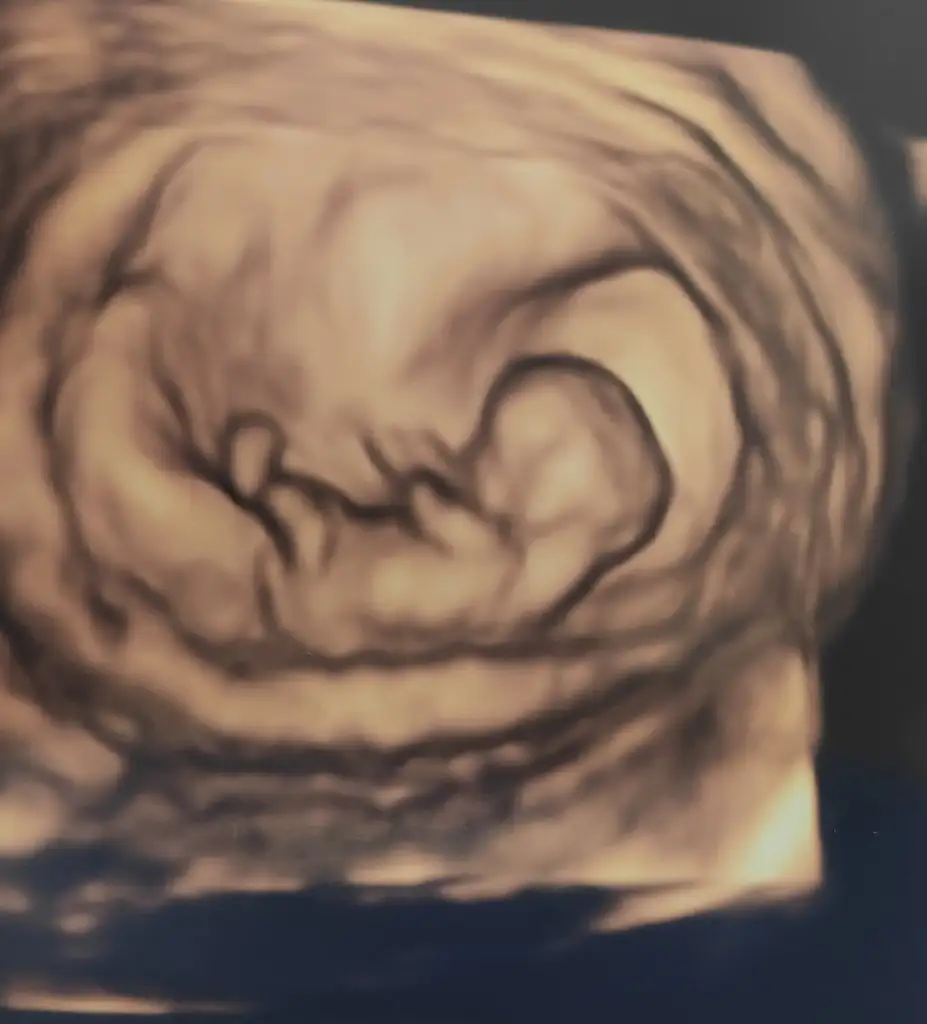

Merhaba 11 haftalık hamileyim bende bir aksilik olmazsa Aralık sonu ile 13 Ocak'a kadar doğum bekliyorum :) Biz cinsiyetini hala sormadık ve öğrenmedik bir süre daha öğrenmeyi düşünmüyorum, eskiden hep kız çocuk isterdim ama nedense oğlum olduğunu hissediyorum,